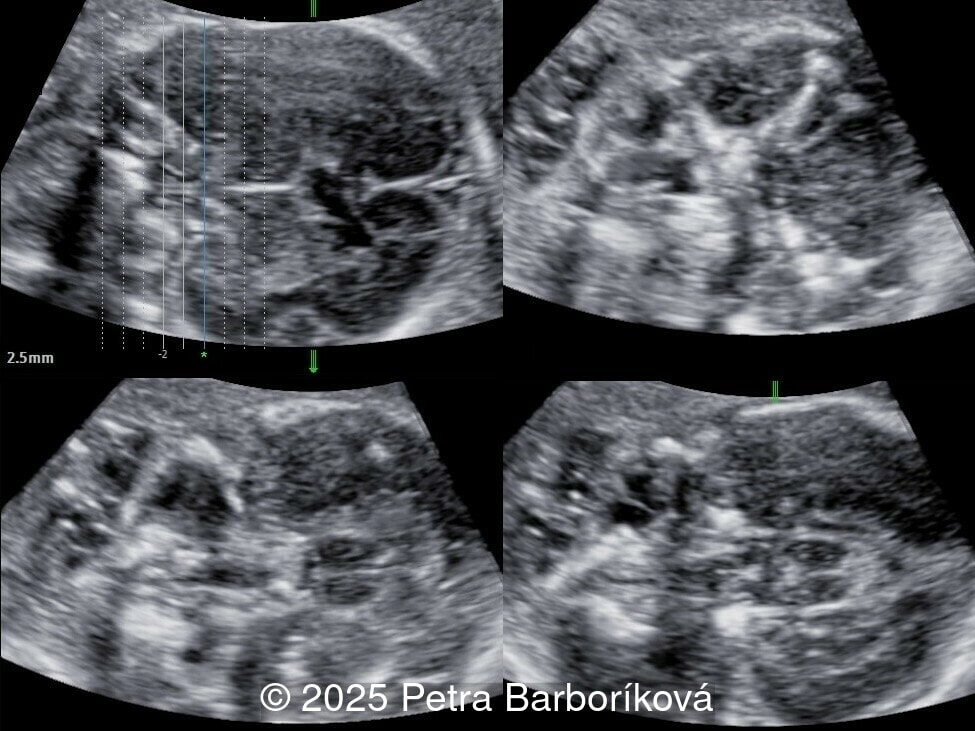

We present a case of agenesis of the cavum septum pellucidum (CSP).

At 20 weeks, detailed ultrasound under conditions of severe oligohydramnios demonstrated absence of the typical box-shaped anechoic structure of the cavum septum pellucidum (CSP). The frontal horns of the lateral ventricles appeared narrow and pointed, giving the characteristic “bull’s horns sign.” Multiplanar and 3D reconstructions confirmed the presence of the corpus callosum, while the CSP was absent. Other midline and posterior fossa structures appeared normal. The optic chiasm was partially visualized, although assessment was limited by technical conditions. Fetal magnetic resonance imaging (MRI) was subsequently performed and confirmed isolated agenesis of the CSP with preserved corpus callosum and posterior fossa structures. The optic chiasm and pituitary stalk are visible in the sellar region, but the pituitary gland itself is not clearly identified in the sella turcica as it is a very small structure. No additional central nervous system anomalies were detected.